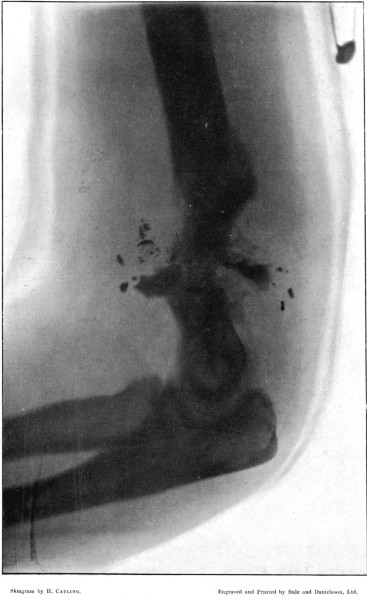

9. Localised Fracture of Humerus Showing Fragmentation of the Bullet190

10. Wedge-shaped Fracture of the Radius192

11. Fracture of the Metacarpus, showing Fragmentation of the Bullet194